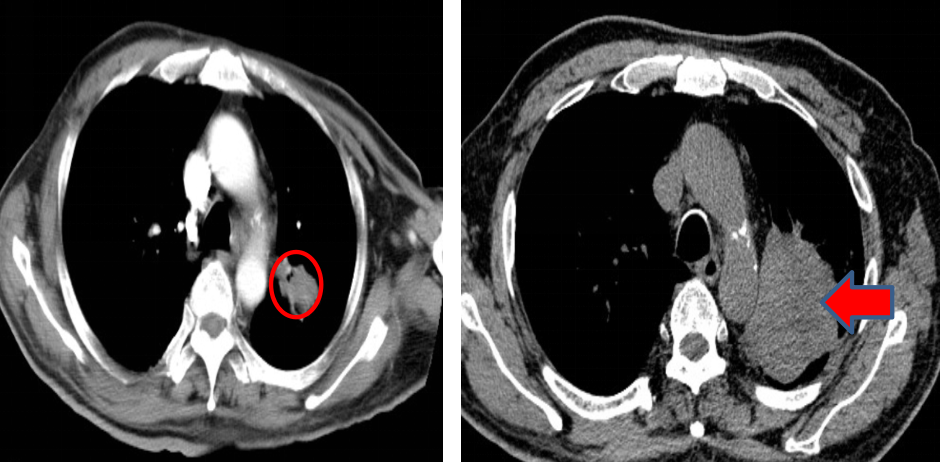

• 影像学检查(2022年9月): PET-CT提示左肺上叶尖后段中央型肺癌可能性大,伴纵膈、左肺门淋巴结及多处骨骼、肝脏转移可能。胸部CT显示左肺上叶团块状软组织影,伴左侧第3前肋溶骨性骨质破坏。头颅MRI未见明确颅内转移。

图片7.png

胸部CT基线(2022年9月)

• 病理学检查(2022年9月): CT引导下经皮肺穿刺活检病理符合鳞状细胞癌。免疫组化结果:CK5/6 (+),P40 (+),CK7 (-),TTF-1 (-),Syn (-),Ki67 (60%+),CD56 (-),LCA (-),Napsin A (-),P63 (+),CK (+)。

临床诊断: 左肺鳞癌 cT4N2M1c(肝、肋骨、锥体转移) IVB期。